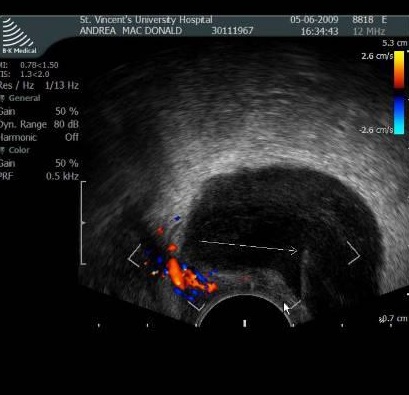

扫描架倾斜,扫描安全的进针途径 ![]() 经阴道(Transvaginal) 经会阴和经直肠穿刺通常也被成为经内腔(transendocavitory)穿刺引流。经阴道对盆腔脓肿进行手术引流是一种较成熟的方法,具有确定的益处,但大多数情况下,积液都使阴道壁移位,使这条通路的应用受到限制。可以在超声引导下进行引流,这样可以准确地将针头或导管放入积液内,这个积液的位置可以毗邻阴道穹窿,但没有使之变形。

最早关于经阴道脓肿引流的报告是在经腹超声引导下进行的。经阴道超声有更高的分辨率,增加了诊断的敏感性以利于更精确地放置导管。这项操作并不一定要在手术室里进行,如果使用了Seldinger技术,在操作过程中联合使用透视,来辅助导管的定位。

无须使用引导扩张器。让病人排空膀胱,处于截石位,用消毒溶液擦拭阴道,同时用一把长钳拉住宫颈固定。通过最开始置入的长穿刺针直接给予局部麻醉。同样也需要给予静脉镇静。因为刺破阴道壁有时候是比较困难的,如果需要插入一个引流管,可以在阴道穹窿上用一把长手术刀切一个小口子,使用引流导管内有金属加硬器的比较优越。如果采用自锁扣式导管,在保留导管时就无须缝合阴道壁或大腿。

Transvaginal Drainage

早期的研究结果表明,经阴道脓肿引流是安全有效的,其成功率可以同经腹引流相比较,但在技术上可能稍难一些。这种方法相对疼痛较少并且能够很好地耐受。对小的非粘性积液单纯应用细针穿刺的作用还有待确定。